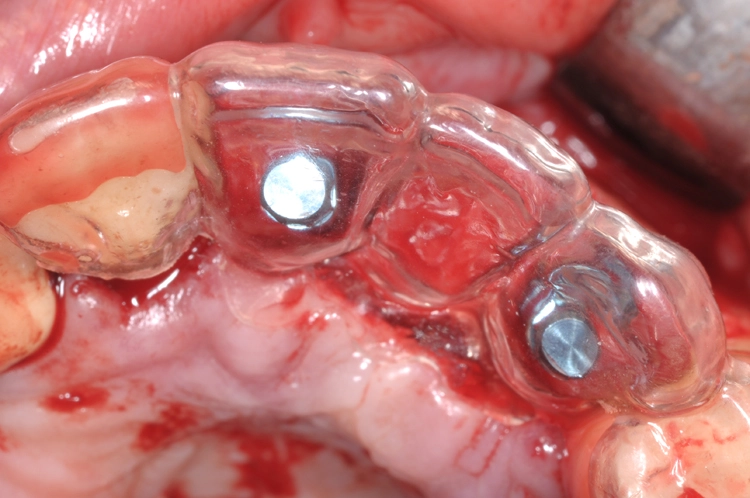

Nach einer viermonatigen Einheilphase erfolgte die Implantation von zwei Straumann® BLT Implantaten mit einer Länge von 12 mm und einem Durchmesser von 4,1 mm im Bereich des aufgebauten Knochens (Ausgangssituation siehe Abb. 8). Vor der Implantation fand vorbereitend eine Glättung der Oberfl äche statt, um scharfe Kanten zu beseitigen (Abb. 9). Für die korrekte prothetische Positionierung der Implantate kamen individuell gefertigte Orientierungsschablonen zum Einsatz, anschließend wurden die Implantate für eine verschraubte Brücke gesetzt (Abb. 10).

Praxis Dr. Robert Würdinger